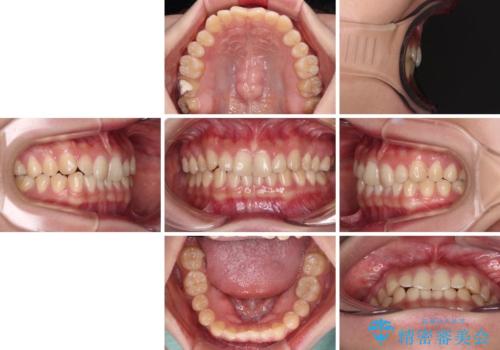

治療途中の奥歯と矯正治療の後戻り インビザライン・ライトによる矯正治療

- 根管治療を行ったままの奥歯と、矯正治療の後戻りを気にして来院された患者様です。

根管治療された歯に症状はなく、オールセラミッククラウンにて補綴治療を行うこととしました。

矯正治療の後戻りは軽微であったため、インビザラインの簡易パッケージであるインビザライン・ライトを用いて歯列を整えることとしました。

クラウンはよりよい咬み合わせで装着したいため、インビザラインを1セット使用して概ね歯列を整えた時点で補綴治療を行い、その後仕上げの矯正治療を行いました。